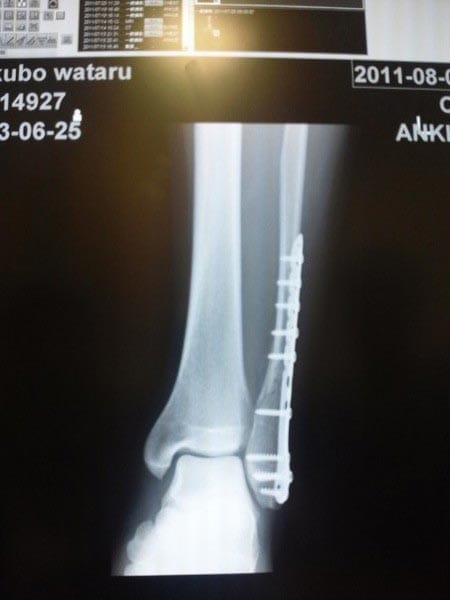

ホームページ更新担当のわたくし大久保は、プライベートでフットサルをしていた際にシュートを打とうとした時に転倒し左足を「複雑骨折・靭帯損傷・くるぶしの骨にもヒビ」という、どうやったら、遊びのフットサルでそうなるんだ!?っていう大ケガをしてしまいまして、救急車で緊急入院半月+自宅療養半月の1ヶ月ほどお休みをいただいておりましたm(__)m

現状はチタンのプレートが入ってサイボーグ化してギブスも外れ、おかげさまでゆっくりですが歩行もできるようになり、本日より出勤しております。